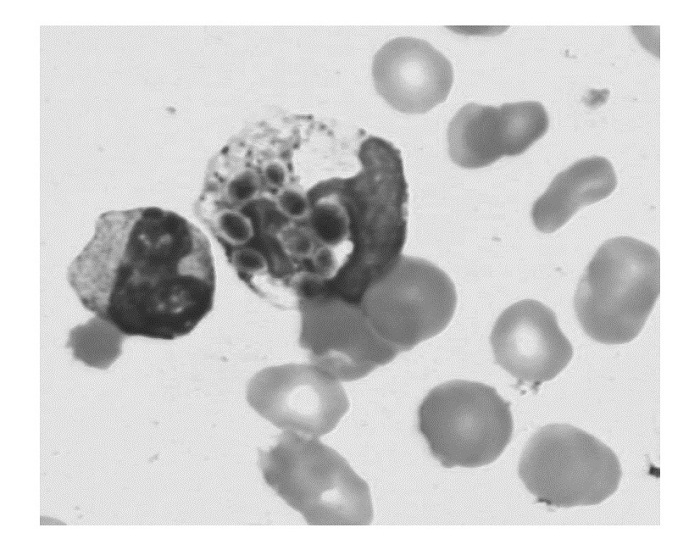

念珠菌菌血症患者血液里的真菌孢子可对所有型号的仪器的WBC、PLT干扰[3]。判断:血涂片上可见到散在或WBC吞噬的真菌孢子, 见图3、图4, WBC和PLT等参数假性增高等。措施:手工计数WBC、PLT。